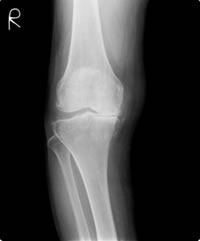

重度変形性膝関節症(グラフ 赤の実線、および図4)は一つ目の山が消失しています。これは歩行中に関節の動きが重度に障害されており、膝がほとんど床からの衝撃を吸収できていないことを示します。

グラフ 歩行中の膝の動き(屈伸運動) 図4.重度変形性膝関節症

図4.重度変形性膝関節症 図5.人工膝関節置換術後